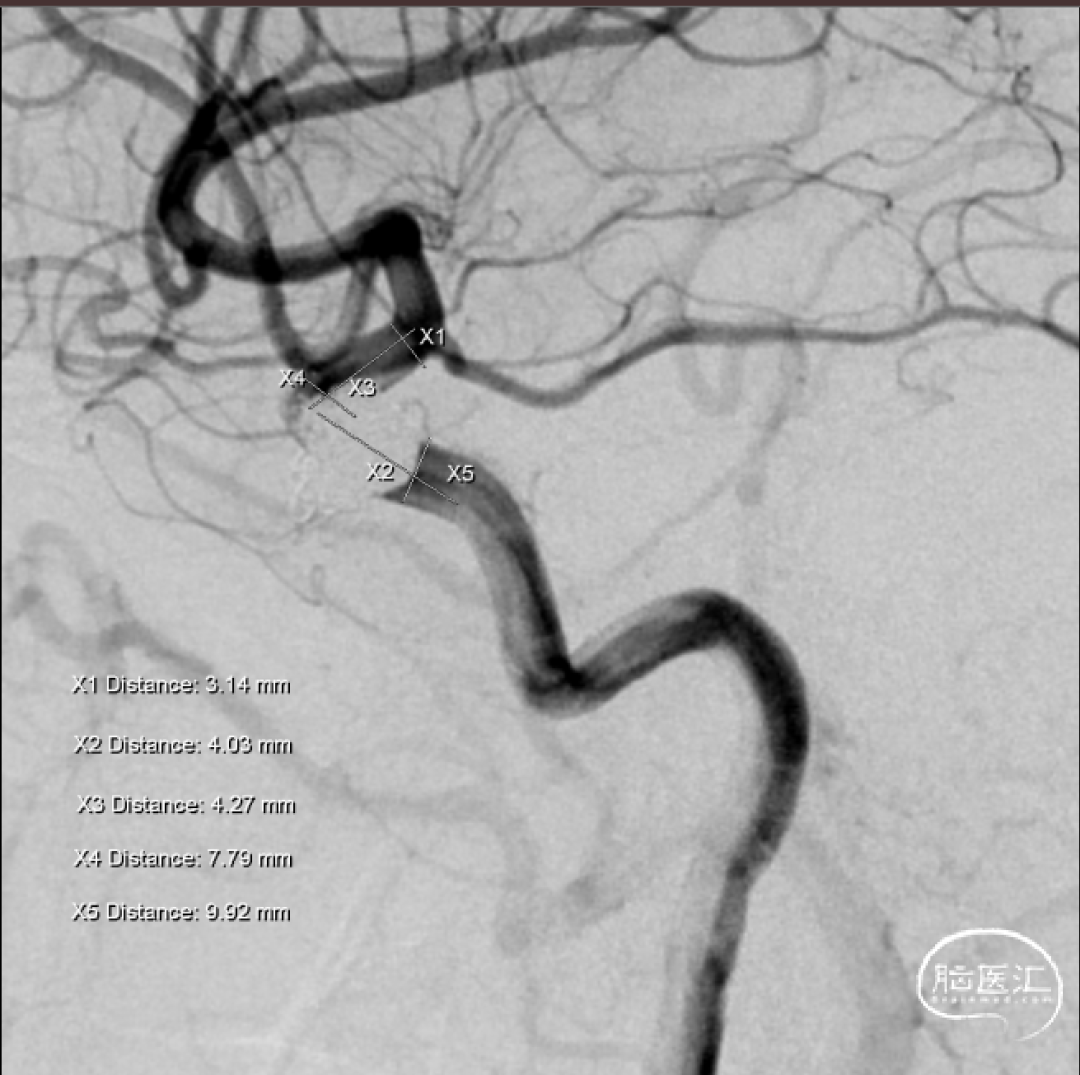

术前造影

术前测量

X1:远端血管直径 | 3.14mm |

X3:瘤颈血管直径 | 4.27mm |

X2:近段血管直径 | 4.02mm |

X4+X5(长度) | 17.79mm |